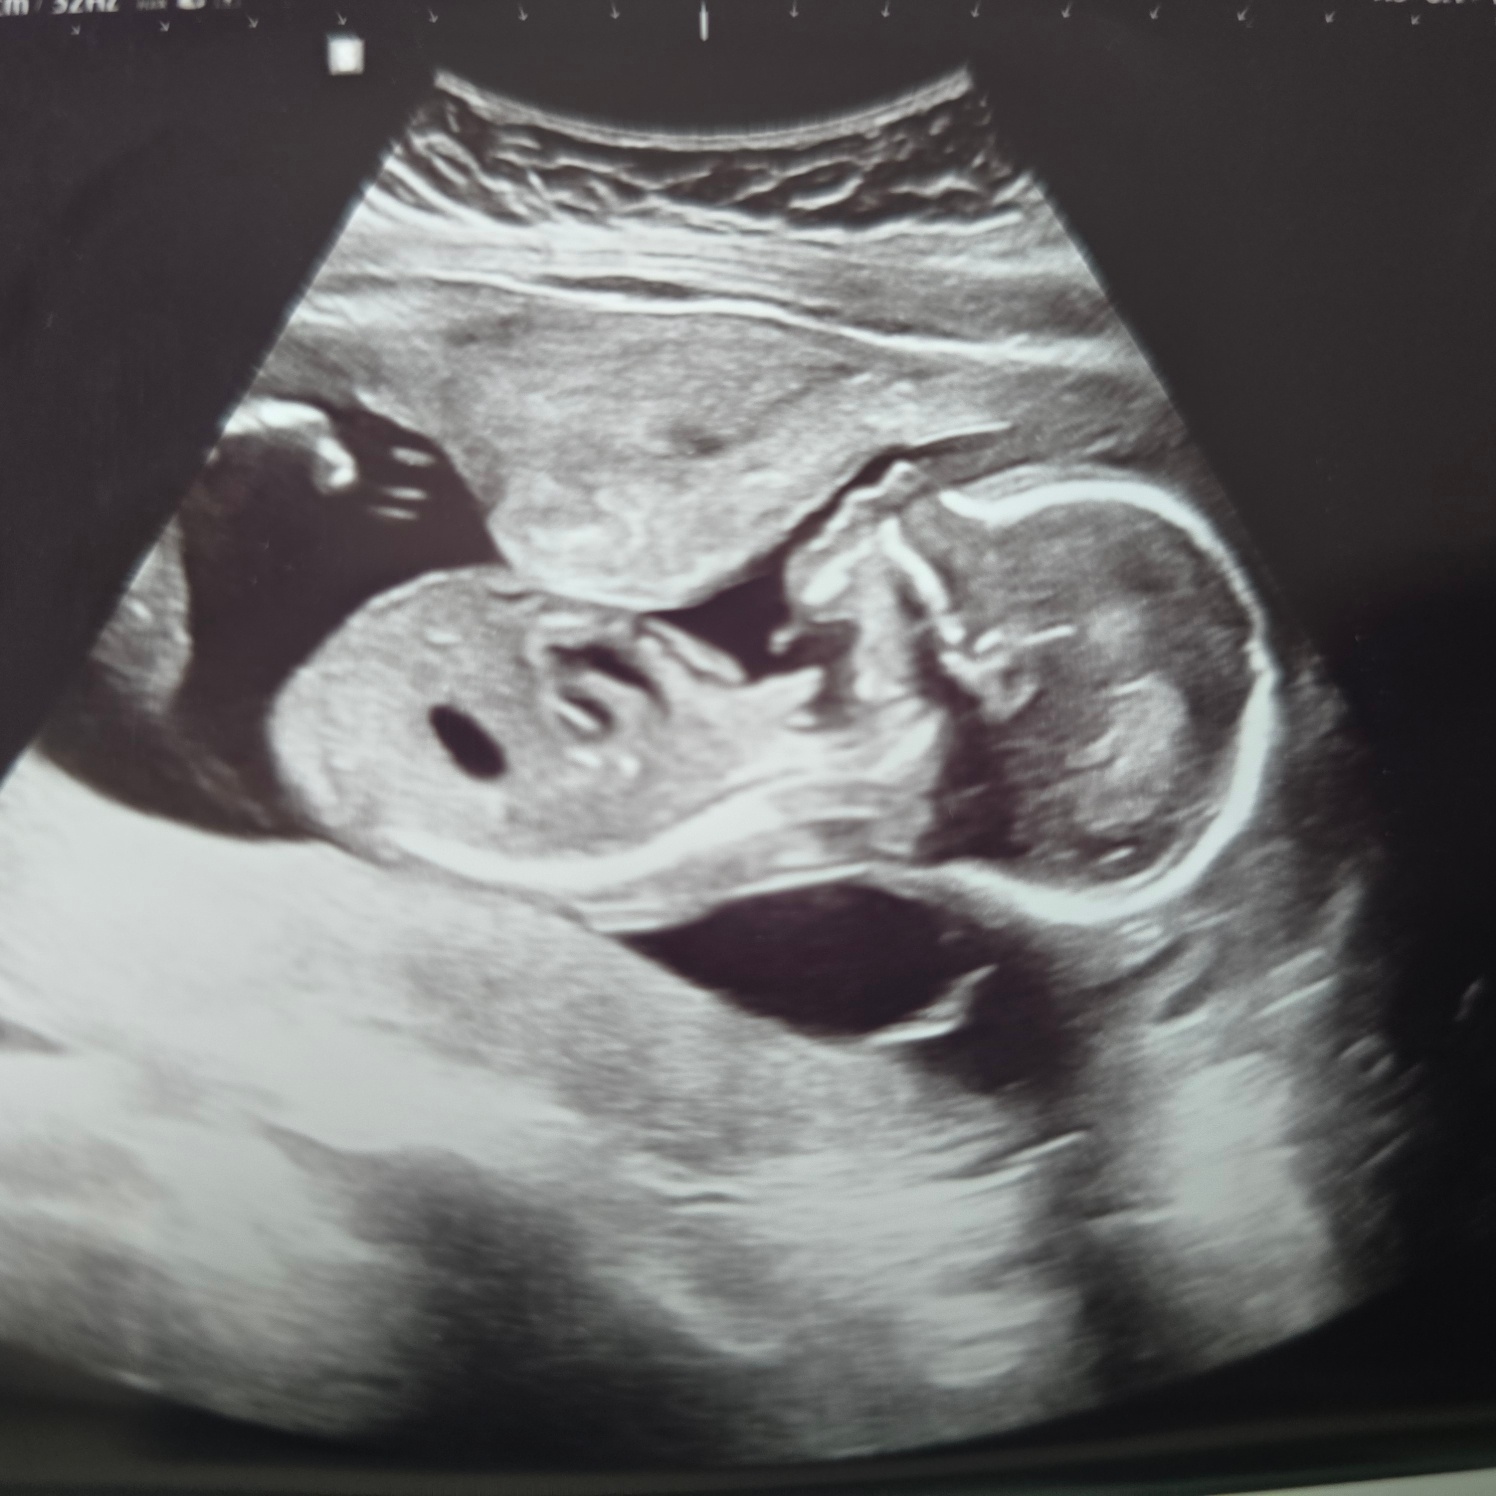

17주 6일 차 - 초음파 확인

양수검사를 하고 아기가 괜찮은지 다음 날 확인하기 위해 병원에서 오라 했다.

이쁜 옆모습을 보여주는 우리 뚝딱이ㅎㅎ

오늘 초음파는 비급여인데 너무 비쌌다..

2분 보면서 8만 원은 너무 한 거 아닌가요..ㅠㅠ

그래도 우리 뚝딱이 건강하고 너무 이쁜 옆모습에 기분이 좋으니 됐다.ㅎㅎ